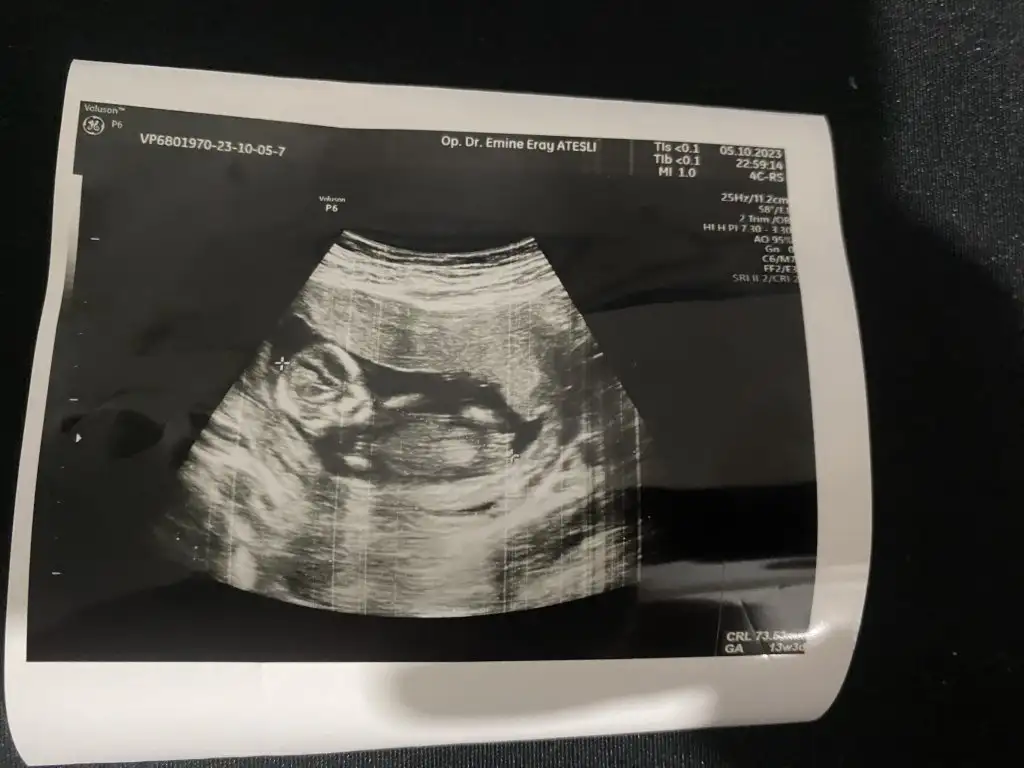

Merhaba lütfen banada bakabilir misiniz 12 haftalikTahmin

Kız gbi cnimMerhaba lütfen banada bakabilir misiniz 12 haftalik